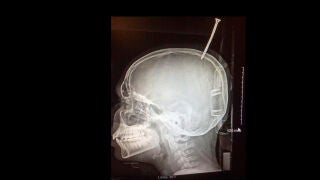

En las radiografías pudieron observar que el tornillo, de una longitud de 15 centímetros, no solo había perforado el cráneo, sino que había penetrado hasta el cerebro.

En concreto, se había clavado en el seno sagital transverso, un canal venoso que permite el drenaje del flujo sanguíneo del área posterior de la cabeza y canaliza la sangre desde el cerebro al corazón, y corría mucho riesgo de sufrir una hemorragia grave. “Estaba a un milímetro de morir desangrado”, afirmó a la CNN Alan Cohen, neurocirujano pediátrico en el Hospital Johns Hopkins que le atendió después.